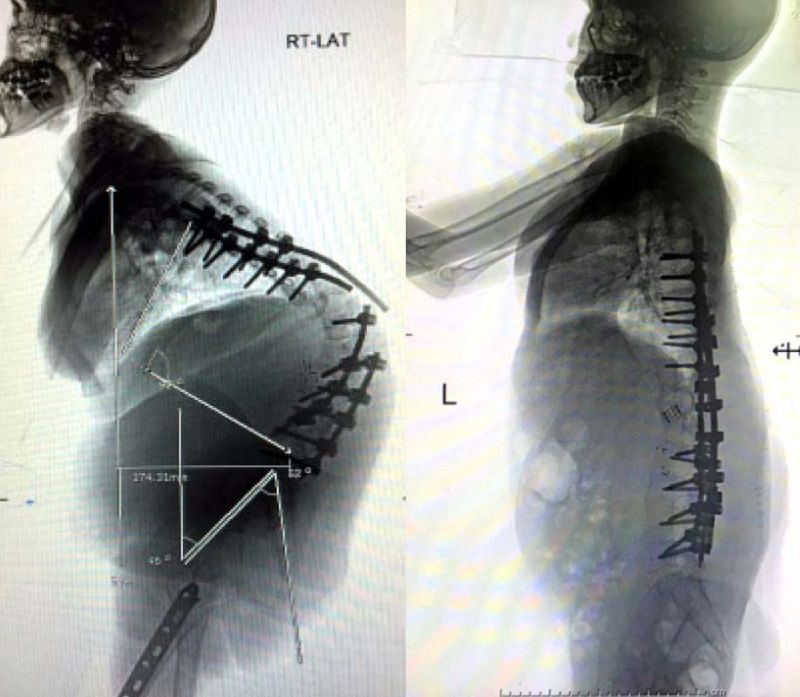

โดยกรณีที่ 1 กระดูกสันหลังคดในเด็กมีสาเหตุมาจากโรคระบบประสาทท้าวแสนปม และผู้ป่วยเคยได้รับการผ่าตัดดามเหล็ก แต่เกิดการหักของเหล็กที่ยึดตรึงกระดูกไว้ ทำให้กระดูกไม่เชื่อมต่อกัน ส่งผลทำให้ผู้ป่วยมีอาการหลังคดโก่งอีกครั้งอย่างรุนแรง และผู้ป่วยจำเป็นต้องได้รับการผ่าตัดแก้ไขซ้ำอีกครั้ง

ผู้ป่วยได้ถูกส่งต่อมารับการรักษาที่รพ.ราชวิถีผู้ป่วยได้รับการ ผ่าตัดด้วยวิธี Full Vertebral Column Resection คือการตัดปล้องกระดูกสันหลังออกทั้งระดับ เพื่อให้สามารถจัดกระดูกสันหลังส่วนอื่นเข้าหาแนวปกติได้มากที่สุด

จุดเด่นความสำเร็จในการผ่าตัดครั้งนี้เมื่อเปรียบเทียบกับผลการรักษาจากต่างประเทศ คือสามารถใช้เวลาผ่าตัดสั้นกว่า คนไข้เสียเลือดระหว่างผ่าตัดน้อยกว่า และประหยัดค่าใช้จ่ายเนื่องจากการผ่าตัดแบบนี้ไม่จำเป็นต้องใช้อุปกรณ์ หรือเทคโนโลยีพิเศษที่มีราคาสูง ซึ่งหลังผ่าตัดคนไข้จะมีกระดูกสันหลังอยู่ในแนวปกติ และหลังตรงขึ้นมีส่วนสูงเพิ่มมากขึ้น ไม่มีภาวะแทรกซ้อนหลังการผ่าตัดและสามารถใช้ชีวิตได้ปกติ เป็นการรายงานการผ่าตัดที่ประสบความสำเร็จครั้งแรกในประเทศไทย